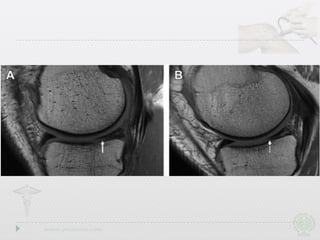

Radial Tears

• Also involvefree edge,but path is perpendicular to long axis • Drastically affect ability to resist hoop stresses • Deeper the tear,the more drastic the biomechanical consequences Radial Tears